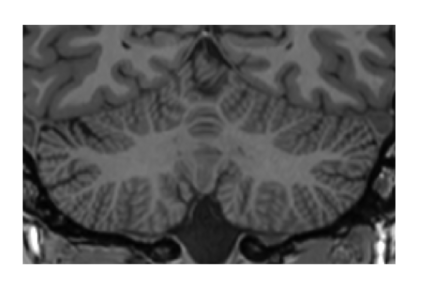

This paper introduces a novel multimodal and high-resolution human brain cerebellum lobule segmentation method. Unlike current tools that operate at standard resolution ($1 \text{ mm}^{3}$) or using mono-modal data, the proposed method improves cerebellum lobule segmentation through the use of a multimodal and ultra-high resolution ($0.125 \text{ mm}^{3}$) training dataset. To develop the method, first, a database of semi-automatically labelled cerebellum lobules was created to train the proposed method with ultra-high resolution T1 and T2 MR images. Then, an ensemble of deep networks has been designed and developed, allowing the proposed method to excel in the complex cerebellum lobule segmentation task, improving precision while being memory efficient. Notably, our approach deviates from the traditional U-Net model by exploring alternative architectures. We have also integrated deep learning with classical machine learning methods incorporating a priori knowledge from multi-atlas segmentation, which improved precision and robustness. Finally, a new online pipeline, named DeepCERES, has been developed to make available the proposed method to the scientific community requiring as input only a single T1 MR image at standard resolution.